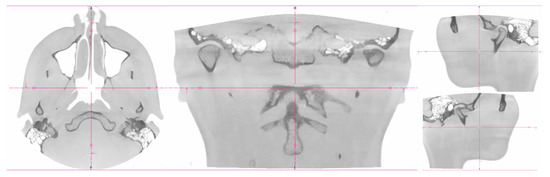

2. Patients, Materials, and Methods

3. Results